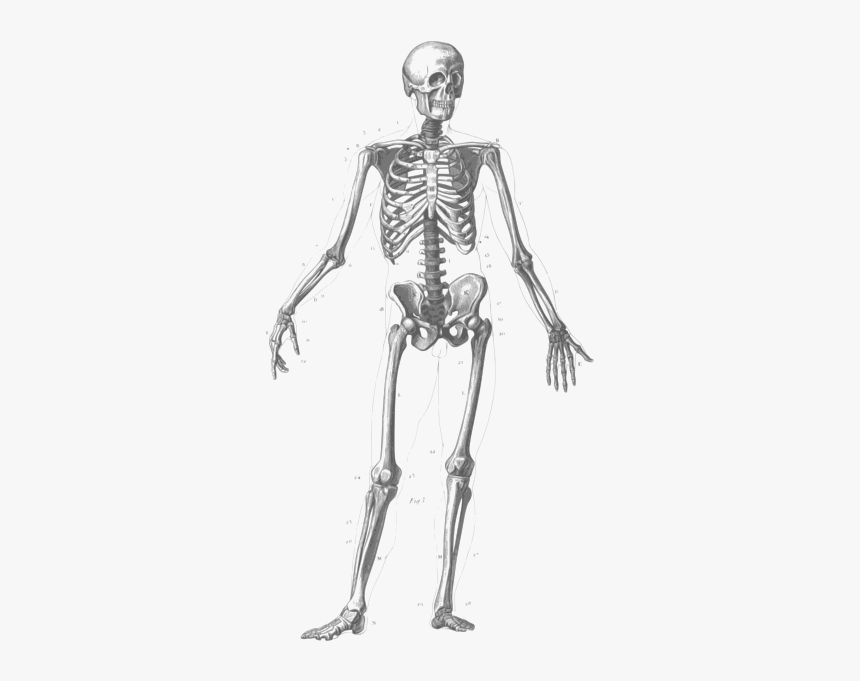

Home > Collections > > Body Figure Drawing Image Body Figure Drawing Image

Download Body Figure Drawing Image (860x681)

Click on the given download button to save Body Figure Drawing Image (860x681) on your device. You can use this image for personal use only. Below you can explore similar drawing art images uploaded by professional artists and published on Tuesday, May 23rd, 2023, at 8:35 am.